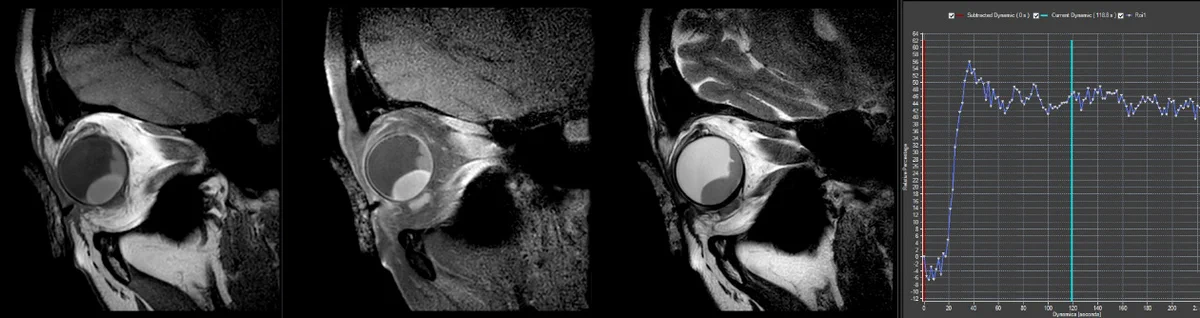

MRI for Ocular Oncology

New MRI technologies to improve the care for eye cancer patients.